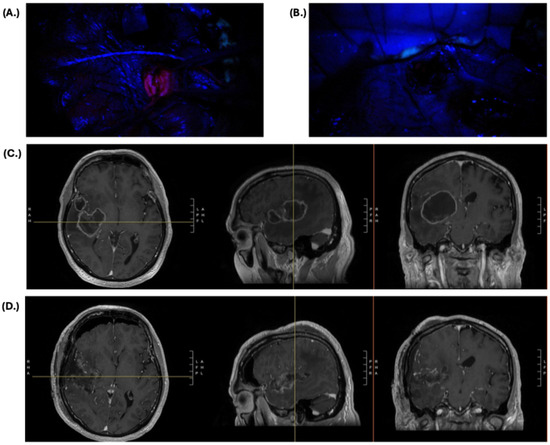

- Marhold, F.; Mercea, P.A.; Scheichel, F.; Berghoff, A.S.; Heicappell, P.; Kiesel, B.; Mischkulnig, M.; Borkovec, M.; Wolfsberger, S.; Woehrer, A.; et al. Detailed Analysis of 5-Aminolevulinic Acid Induced Fluorescence in Different Brain Metastases at Two Specialized Neurosurgical Centers: Experience in 157 Cases. J. Neurosurg. 2020, 133, 1032–1043. [Google Scholar] [CrossRef]

- Mercea, P.A.; Mischkulnig, M.; Kiesel, B.; Wadiura, L.I.; Roetzer, T.; Prihoda, R.; Heicappell, P.; Kreminger, J.; Furtner, J.; Woehrer, A.; et al. Prognostic Value of 5-ALA Fluorescence, Tumor Cell Infiltration and Angiogenesis in the Peritumoral Brain Tissue of Brain Metastases. Cancers 2021, 13, 603. [Google Scholar] [CrossRef]